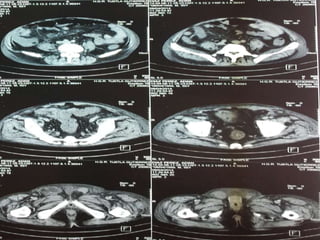

Anomalías Genitourinarias

11% de los pacientes pueden presentar estenosis

pieloureteral y/o hidronefrosis.